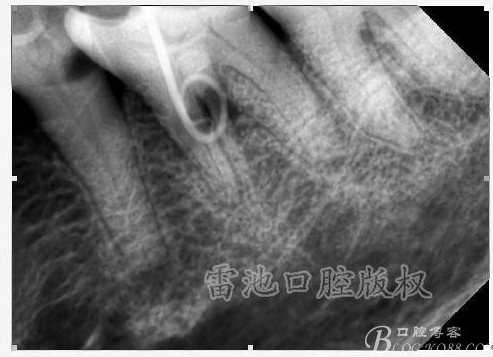

C、牙根的折裂與隱裂 包括橫折,縱折,或者斜折,外傷類的不用討論,主要是某些特殊原因比如牙齒本身結構先天性缺陷再配合后天因素如牙合創(chuàng)傷、咬合平衡發(fā)生改變導致應力集中,或者某次瞬間的咬合暴力等一種或者多種因素作用的結果,具體什么原因這個要從多方面因素權衡來判斷,比如牙齒的松動度,詢問病史,找不出其它原因時的重點懷疑,牙齒本事是否處于合應力集中的區(qū)域,是否有不良修復設計等等,具體可以通過臨床“理化檢查(冷熱,叩診等)”再結合數值化小牙片,牙髓活力測定,以及CBCT等來綜合判斷,重點懷疑牙為上頜的4/5的頰或者腭根,尤其是4或者5的遠中已是游離缺失或者單端橋等,6的腭根以及下頜的4/5/6都是重點懷疑對象,而最難診斷的是牙根的隱裂,即使使用CBCT有時候也沒辦法確診;